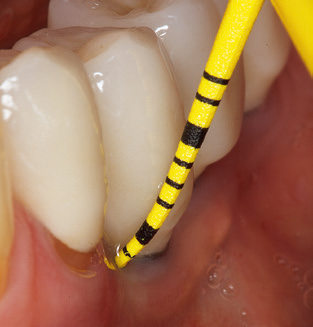

The current working concept for SPT

Fig. 4: Flexible probes with millimetre markings are recommended for the probing of dental implants (e.g. Colorvue Kit PCV11KIT6, Hu­Friedy). – Fig. 5a and b: A straight working tip (1P, W&H Dentalwerk Bürmoos GmbH) is a suitable instrument for use on all natural teeth. – Fig. 6: Curved working tips (3Pr/3Pl, W&H Dentalwerk Bürmoos GmbH) lend themselves to the processing of difficult-to-reach areas of the tooth and root surfaces (e.g. furcations). – Fig. 7: The tapered, hexagonal implant cleaning tip (1I, W&H Dentalwerk Bürmoos GmbH) permits atraumatic and efficient cleaning of the crown and abutment surfaces. – Fig. 8: Titanium and carbon curettes are suitable instruments for the manual cleaning of the implant surfaces.

Good illumination of the working field facilitates the process considerably. The system used by the authors achieves this thanks to a 5x LED ring integrated in the handpiece. Naturally, a range of working tips for different indications is also offered. A straight, universally employable tip is the basic instrument required for machine cleaning of natural teeth (Fig. 5a and b). Curved tips, which allow access to exposed furcations, are also available for hard-to-reach areas in the posterior region (Fig. 6).